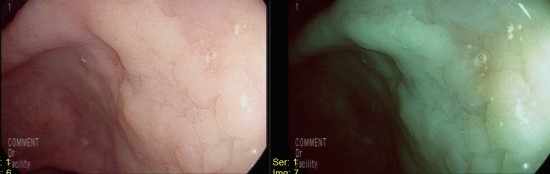

대변검사 양성으로 처음 시행하는 대장내시경

직장, S결장 이행부에 2.5cm, Vi pit pattern을 보이는 종괴

조직검사상 대장선암

Colon, rectosigmoid junction, 15cm from anal verge, colonoscopic biopsy;

Adenocarcinoma, well differentiated

용종발견율이 40%에 육박하므로 최소 50대 이후에는 정기적인 대장내시경이 필요함.

(근래 20-30대에서도 고등급의 선종이 발견되어 용종절제술을 시행하기도 하였음.)

용종의 경우 출혈가능성이 떨어지므로 국가검진의 대변검사만으로는 유무를 확인할 수 없음.

대변검사 양성의 경우 진행한 선종, 대장선암이거나 혹은 이외 거짓양성결과일 수 있음.